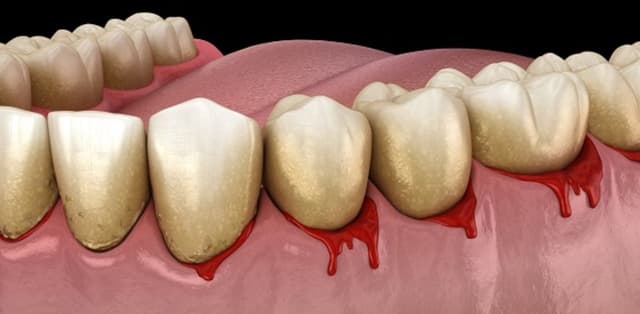

Cao răng là tác nhân chính gây ra một số bệnh lý nha khoa nguy hiểm như sâu răng, viêm nha chu, hôi miệng… Bởi vậy, các bác sĩ luôn khuyến cáo mọi người cần thực hiện lấy cao răng thường xuyên tại nha khoa để phòng ngừa bệnh lý. Việc tìm hiểu nguyên nhân […]

Không chỉ gây mất thẩm mỹ, cao răng còn là môi trường lý tưởng để vi khuẩn phát triển gây ra các bệnh lý răng miệng. Do vậy, các bác sĩ luôn khuyến cáo mọi người cần phải lấy cao răng thường xuyên để ngăn chặn các tác nhân có hại tấn công. Vậy lấy […]